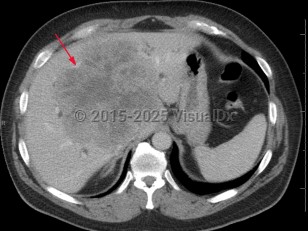

Acinar cell carcinoma is a rare malignant exocrine tumor of the pancreas resembling cells of the pancreatic acini. It comprises less than 1% of all pancreatic neoplasms and is usually a solid tumor. Its gross appearance is a pink to tan homogeneous growth. Tumors may grow to over 10 cm in diameter. Although seen most frequently in males of Northern European ancestry who are middle-aged or older, acinar cell carcinoma can occur at any age.

Findings include abdominal pain, a pancreatic mass, nausea, fatigue, weakness, elevated lipase, and weight loss. Some patients present with Schmid's triad (subcutaneous fat necrosis, polyarthritis, and eosinophilia) caused by elevated lipase secreted by the tumor.